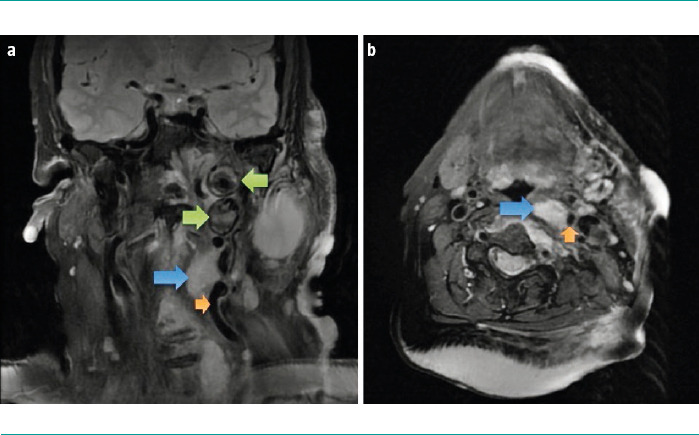

Case report: A 67-year-old woman with a genetic diagnosis of NF1 and a history of multiple exeresis of neurofibromas in the left cervical region. The patient presented with a painful flare-up and swelling in the region. A cervical magnetic resonance imaging was performed, which showed signs of plexiform neurinoma growth and a lesion suggestive of aneurysm in the left cervical internal carotid artery. A subsequent computed tomographic angiography confirmed the presence of a thrombosed aneurysm with associated critical stenosis, and identified three additional aneurysms in the proximal left vertebral artery. Given the asymptomatic presentation and adequate haemodynamic compensation, the patient was prescribed a conservative treatment and clinicoradiological follow-up.